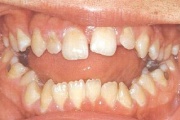

Puudub ülemine tsentraalne intsisiiv, kuid külgmised lõikehambad on juba lõikunud.

Turritavad ülemised lõikehambad.

ruumipuudus eesmiste hammaste osas